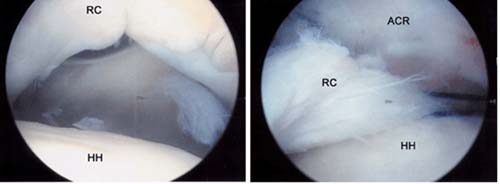

Left, Arthroscopic view of rotator cuff tear. A large gap can be seen between the

edge of the rotator cuff and humeral head.